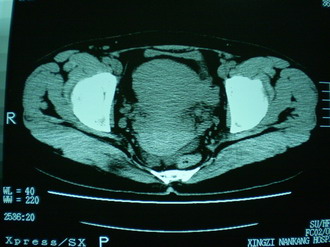

子宫明显前倾,增大,宫颈增大呈分叶状。子宫直肠窝见不规则形水样低密度。(膀胱胀尿不理想)

考虑:1、宫颈部占位;

2、子宫直肠窝少量积液(盆腔炎所致)。

考虑:1、宫颈部占位(宫颈癌?);

2、子宫直肠窝少量积液。

宫颈部占位(肌瘤,癌肿);建议强化.

子宫明显前倾,增大,宫颈增大呈分叶状。子宫直肠窝见不规则形水样低密度。